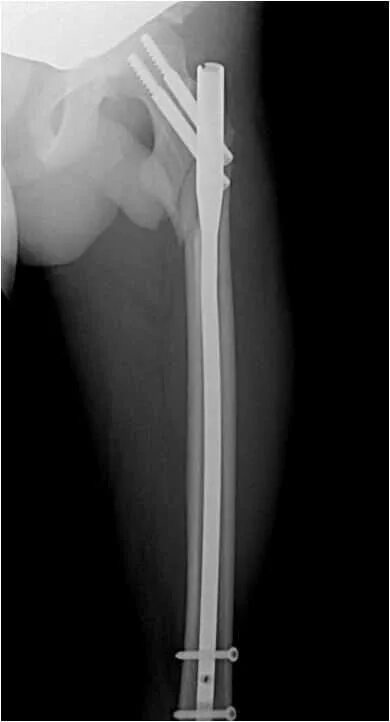

Остеосинтез чрезвертельного перелома